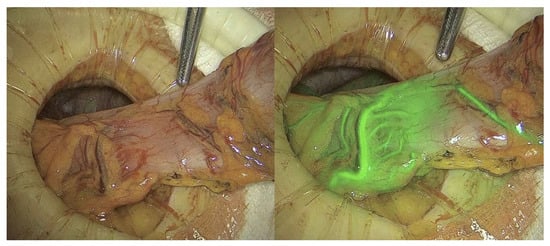

3.5. Sentinel Lymph Node Assessment

Figure 4. Sentinel lymph node identification using white light (left) and indocyanine green imaging (right). Courtesy of the International Society for Fluorescence Guided Surgery (ISFGS).